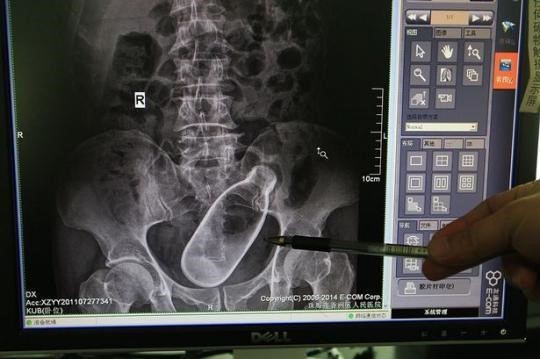

병원 진료를 받게 된 남성은 엑스레이 촬영을 하였으며 엑스레이 사진에는 20cm 길이의 덤벨이 직장과 결장이 만나는 곳에 박혀있는 모습이 포착되었습니다.

의료진은 수술 도구를 사용하여 덤벨을 제거하려 시도하였지만 불가능했다고 하며 결국 의사가 직접 손을 집어넣어 덤벨을 빼냈다고 합니다.